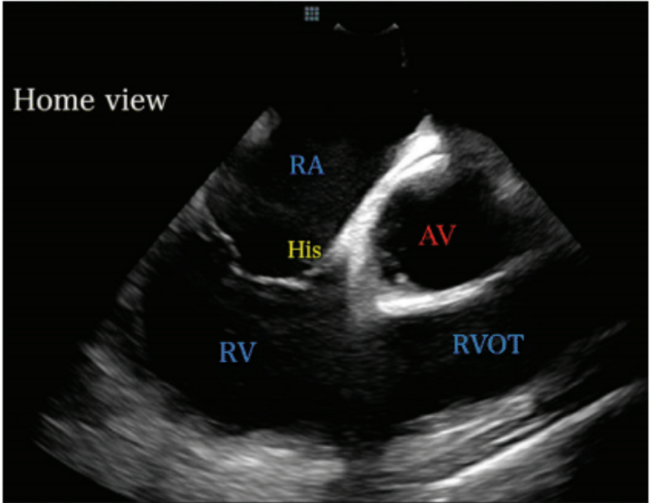

AV=aortic valve; His=bundle of His area; RA=right atrium; RV=right ventricle; RVOT=right ventricular outflow tract.

Once in the RA, the ICE catheter was minimally rotated clockwise or counterclockwise until the “home view” was seen. The home view is where the RA, tricuspid valve (TV), right ventricle (RV), and aortic valve (AV) are seen (Figure 1). From this position, an anterior curve was applied to the ICE catheter prior to advancing the ICE catheter across the tricuspid valve and into the RV. Once in the RV, the anterior curve was released and the catheter was used to assess for the presence of any pericardial effusion around the RV (Figure 2). To assess for fluid around the LV, the ICE catheter was rotated clockwise until the LV was in view (Figure 3). These images were stored and served as a useful comparator in the event of hypotension later in the case.